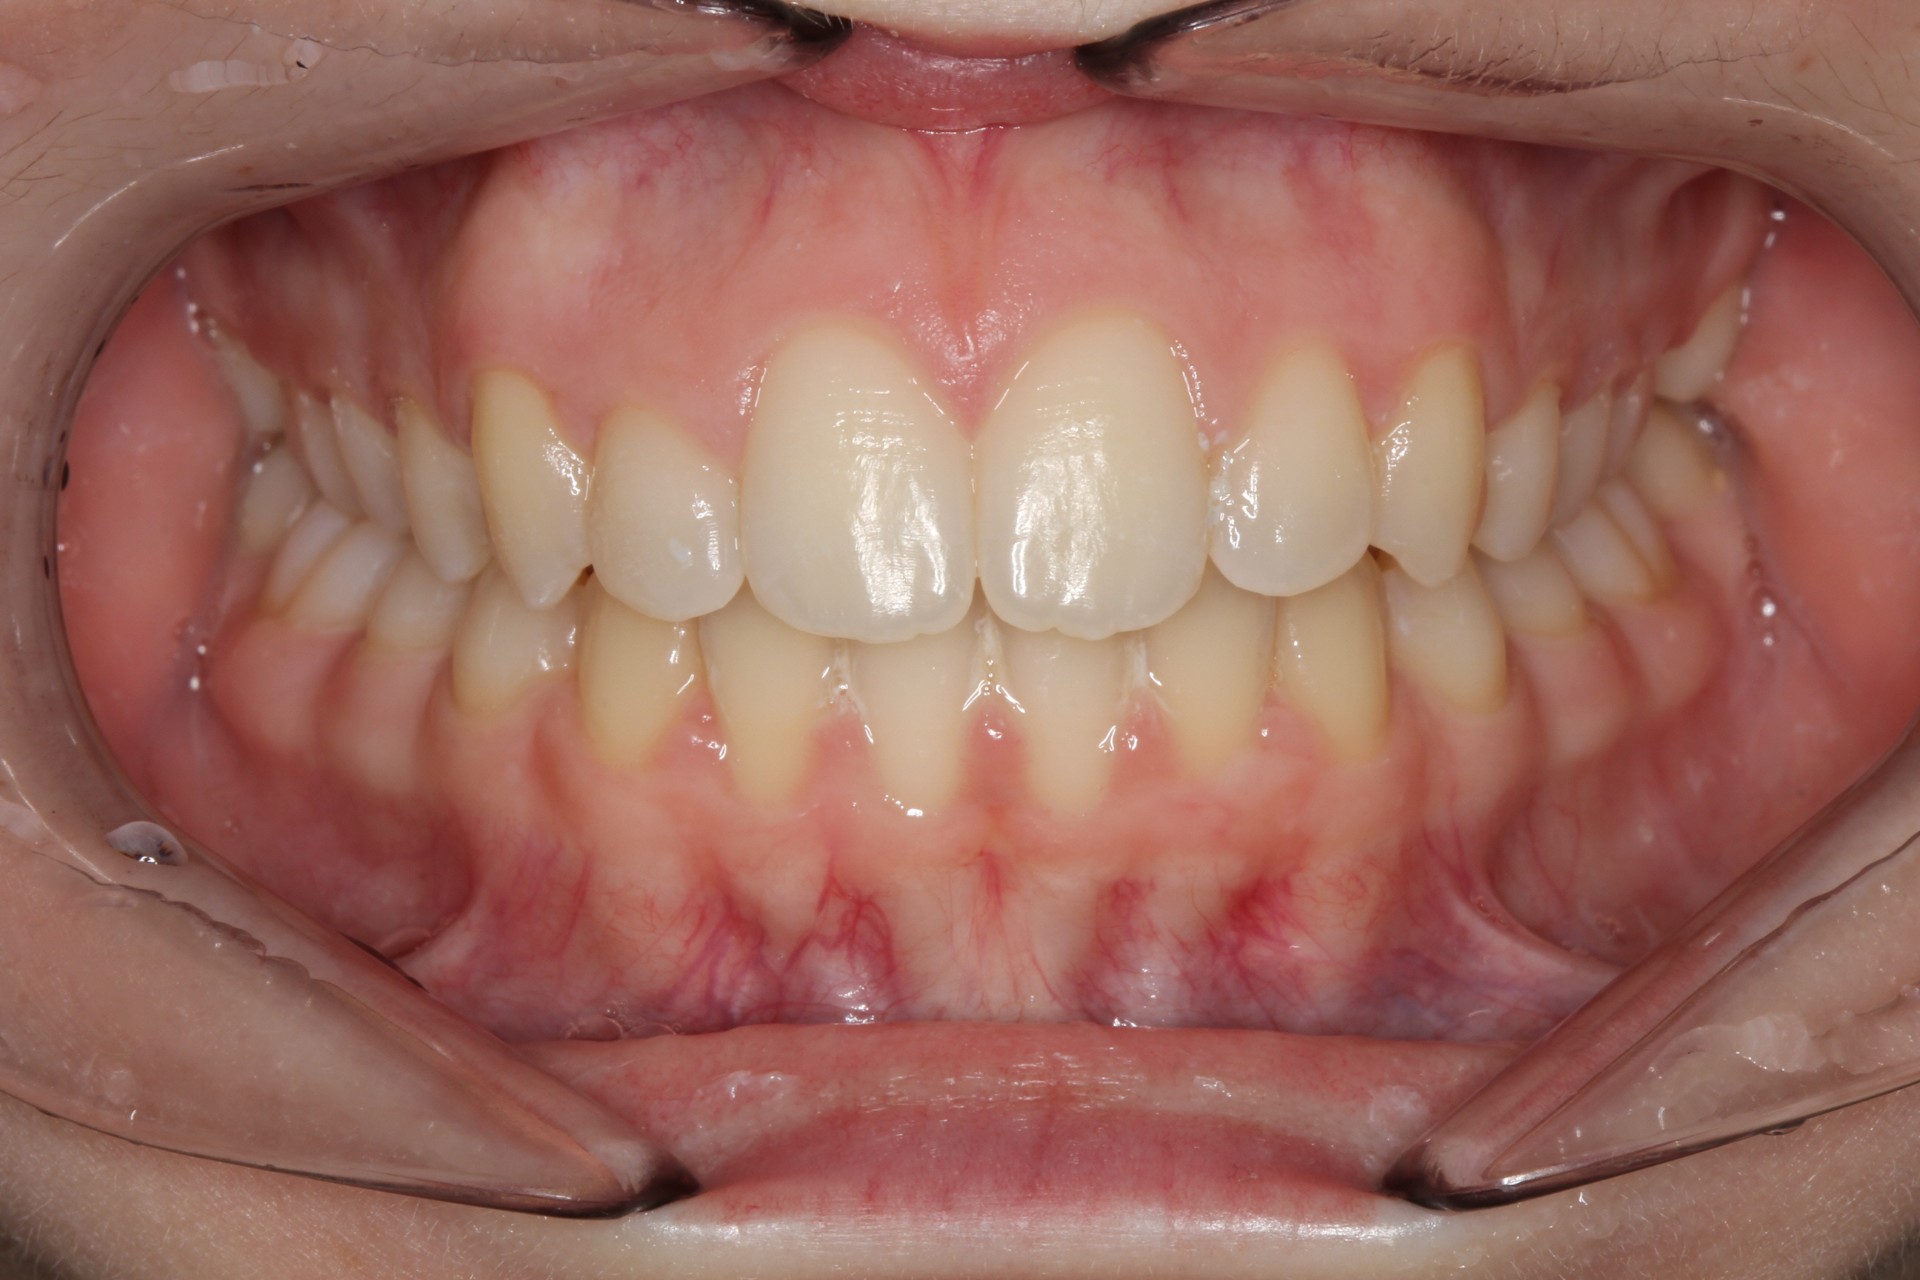

Crowding – Child case